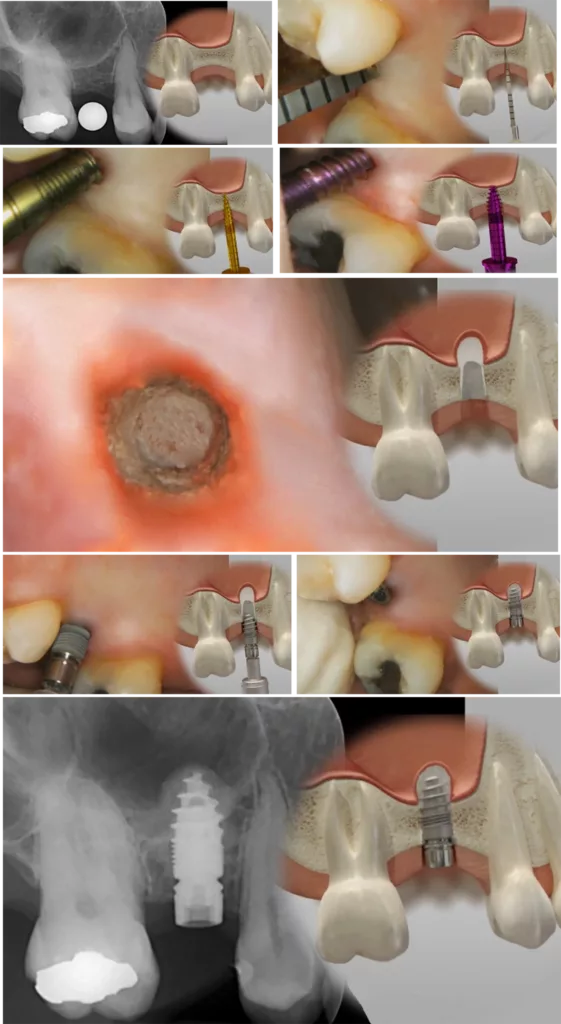

Die Tatsache, dass man beim patentiert-zweiteiligen Champions (R)Evolution Implantat mit bakteriendichtem Innenkonus mit integriertem Hexadapter zugleich den Gingivaformer, als scanbares Abformungstool und die Abutment-Halteschraube mit inseriert, macht das Champions System für MIMI ideal konzipiert. Überdies kann man mit Leichtigkeit ein Emergenzprofil innerhalb einer Woche kreieren. Dazu werden einfach sechs verschiedene PEEK-Gingiva-Clix über den Shuttle gesteckt (Abb. 1).

Auch interne, direkte Sinuslifte (IDS) sind mit MIMI problemlos möglich. Mit konischen Dreikantbohrern und inzwischen fast nur noch „digital“ wird die Gegenkortikalis des Kieferhöhlenbodens „aufgespürt“ und mit abgeflachten WS-Condensern mit 30 U/Min. und 30 bis 40 Ncm eröffnet, um die Schneidersche Membran bis zu 5 mm unkompliziert mit Knochenersatzmaterial (Smart Grinder oder Ethoss) anzuheben. Diese MIMI-VI-Implantation kann man simultan mit dem IDS durchführen, wenn mindestens 3 mm Restknochenhöhe vorhanden ist. Dabei sollte man allerdings nicht, wie sonst empfohlen, 1 bis 2 mm subkrestal implantieren, sondern äquikrestal, d.h. auf „Bone-Level“, damit das Mikrogewinde des Champions voll in der Restknochenhöhe gefasst ist. Auch in IDS-Fällen warten wir mindestens vier Monate bis zum Einsetzen der Krone (Abb. 4).

Durch die Reduktion der Anzahl der erforderlichen Sitzungen von fünf (KIV) auf zwei (MIMI), die Verkürzung der Gesamtdauer (von ca. 180 auf ca. 60 Min.) inklusive des Einsetzens des Zahnersatzes sowie die Vermeidung der Verschraubung im Implantatkörper hat das MIMI-Verfahren für uns die Implantologie grundlegend und positiv revolutioniert (Abb. 5).